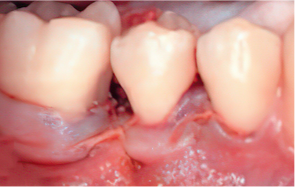

엠도게인 수술과정

STEP 01

잇몸을 절개

STEP 02

Scaling Root Planning을 실시

-

STEP 03

치석 및 치태 등 제거

STEP 04

엠도게인 도포

STEP 05

클렌징

STEP 06

판막을 봉합

Before & After